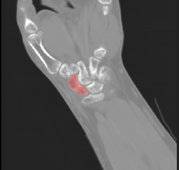

充分发挥专业优势,同积水潭医院深入开展红色“1+1”支部共建活动,通过建立手舟骨CT和金标准数据库,显著提高手术效率及准确率。该技术应用以来,受益人数上万人。

技术钻研,助力智慧医疗。MedAI实验室与301医院、中日友好医院、北京协和医院等多家三甲医院合作,将信息技术与医疗相结合,研发了一系列医学影像智能分析算法,为上千余例手术提供技术支持,促进了学科交叉发展和成果落地,以科技助力智慧医疗。